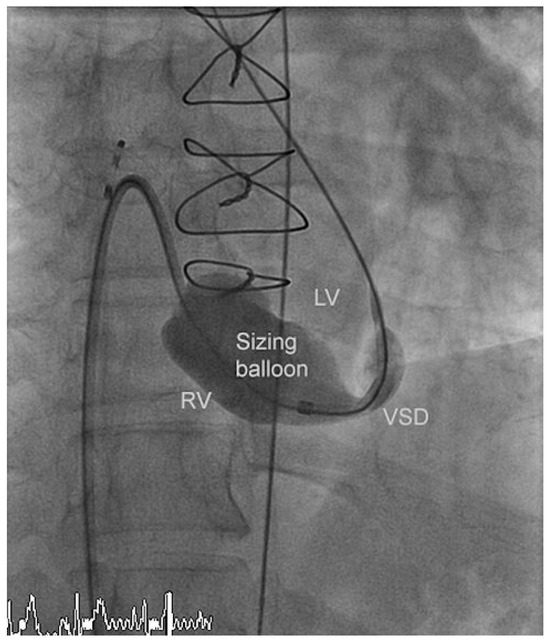

A Case for Incidental Coronary Angiography During Percutaneous Closure of the Patent Foramen Ovale?

by Nikesh Raj Shrestha, Thomas Pilgrim, Alexander Kadner and Bernhard Meier

Cardiovasc. Med. 2011, 14(10), 283; https://doi.org/10.4414/cvm.2011.01616 - 26 Oct 2011

A 42-year-old male had undergone a successful closure of a patent foramen ovale (PFO) seven years earlier for cryptogenic stroke. In spite of several risk factors an incidental coronary angiogram was not performed due to his young age (35 years at that time). [...] Read more.

A 42-year-old male had undergone a successful closure of a patent foramen ovale (PFO) seven years earlier for cryptogenic stroke. In spite of several risk factors an incidental coronary angiogram was not performed due to his young age (35 years at that time). Seven years later a myocardial infarction (MI) caused an apical ventricular septal defect (VSD) necessitating a surgical correction. Finally device closure became necessary due to patch dehiscence. Incidental coronary angiography on the occasion of PFO closure would have resulted i n timely coronary treatment by acetylsalicylic acid and a statin and perhaps coronary angioplasty. The MI and its complicated course could most likely have been prevented. Full article

Show Figures

Figure 1